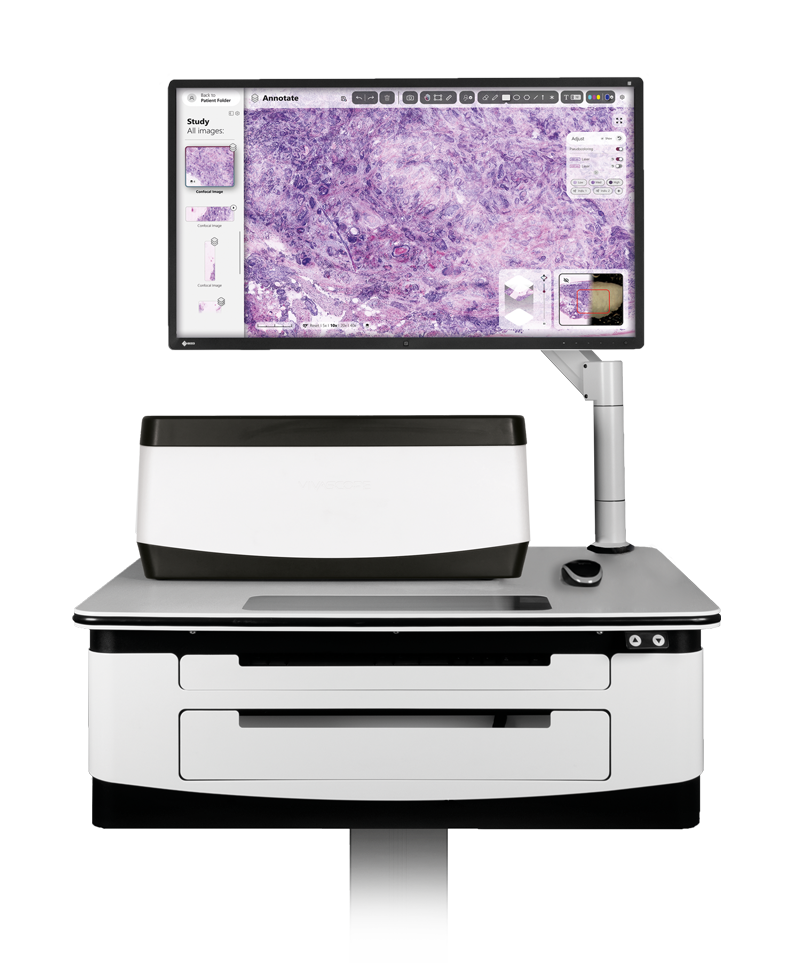

Fresh tissue can be examined immediately after an excision without lengthy procedures. This allows for the direct assessment of the specimen in the operating room. All packed in our “moveable” laboratory, the VivaScope 2500. The device is capable of working within a hospital’s DICOM environment to enable storage, search, viewing, scheduling and backup of acquired images.

The VivaScope technology is based on confocal microscopy (CLSM) and acquires images of superb optical resolution and contrast. The VivaScope 2500 images allow seamless zoom with up to 500x magnification and a great sample size.

The microscope can be installed on a movable table and thus be used in different locations and surgery rooms in clinics / hospitals.